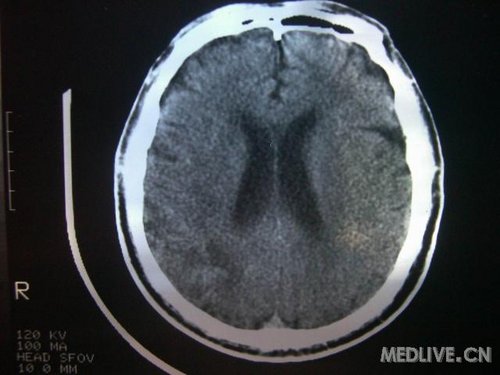

病人男性 73岁 市民 以“幻听、幻视两天,言语含糊、精神错乱一天”入院。

两天前无诱因出现幻听、幻视,描素眼前有彩色的圆圈,听见有人说话(但说什么不详),一天前出现胡言乱语,言语含糊,精神错乱,问话不答,行走略有不稳,来我院就诊,门诊头CT检查:(下面有片)入院后查体不合作,表情淡漠,问话不答,大致检查了一下,颅神经未见明显异常,颈软,右手活动似忽略差。其他检查不配合。脑电图:广泛轻-中度异常。

既往史:半年前曾患“右侧脑梗塞”但无明显后遗症,生活能自理,无高血压、糖尿病、心脏病史。

先传半年前的片子:

此次入院时的片子: